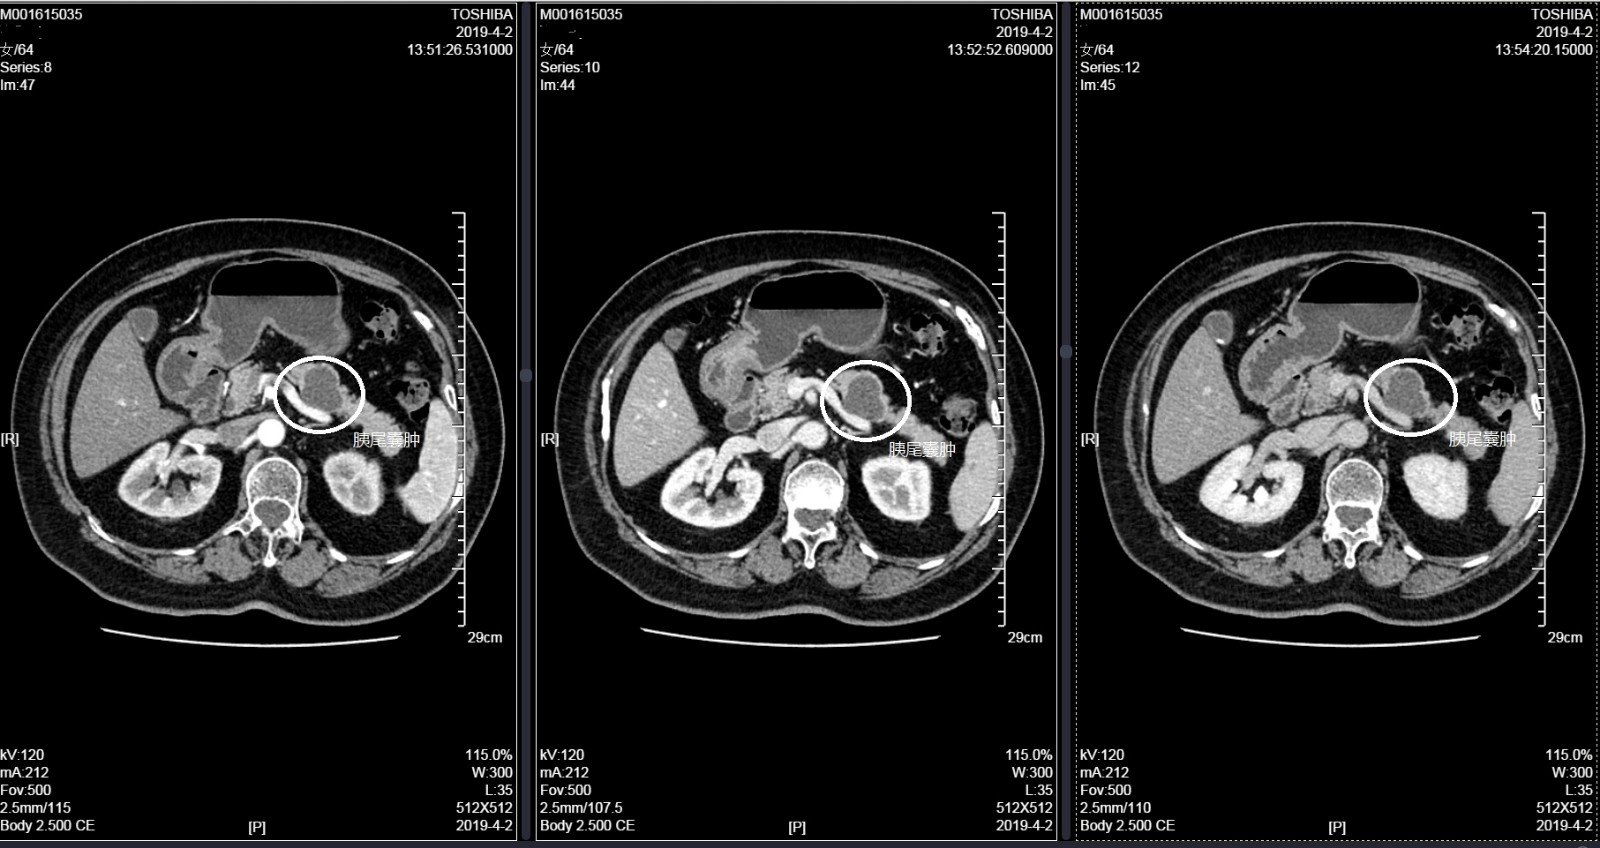

胰腺囊性肿瘤:分支胰管型ipmn癌前病变的. 来自pancman-lc - 微博